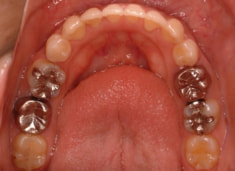

治療開始時

治療開始から約1年2ヶ月後